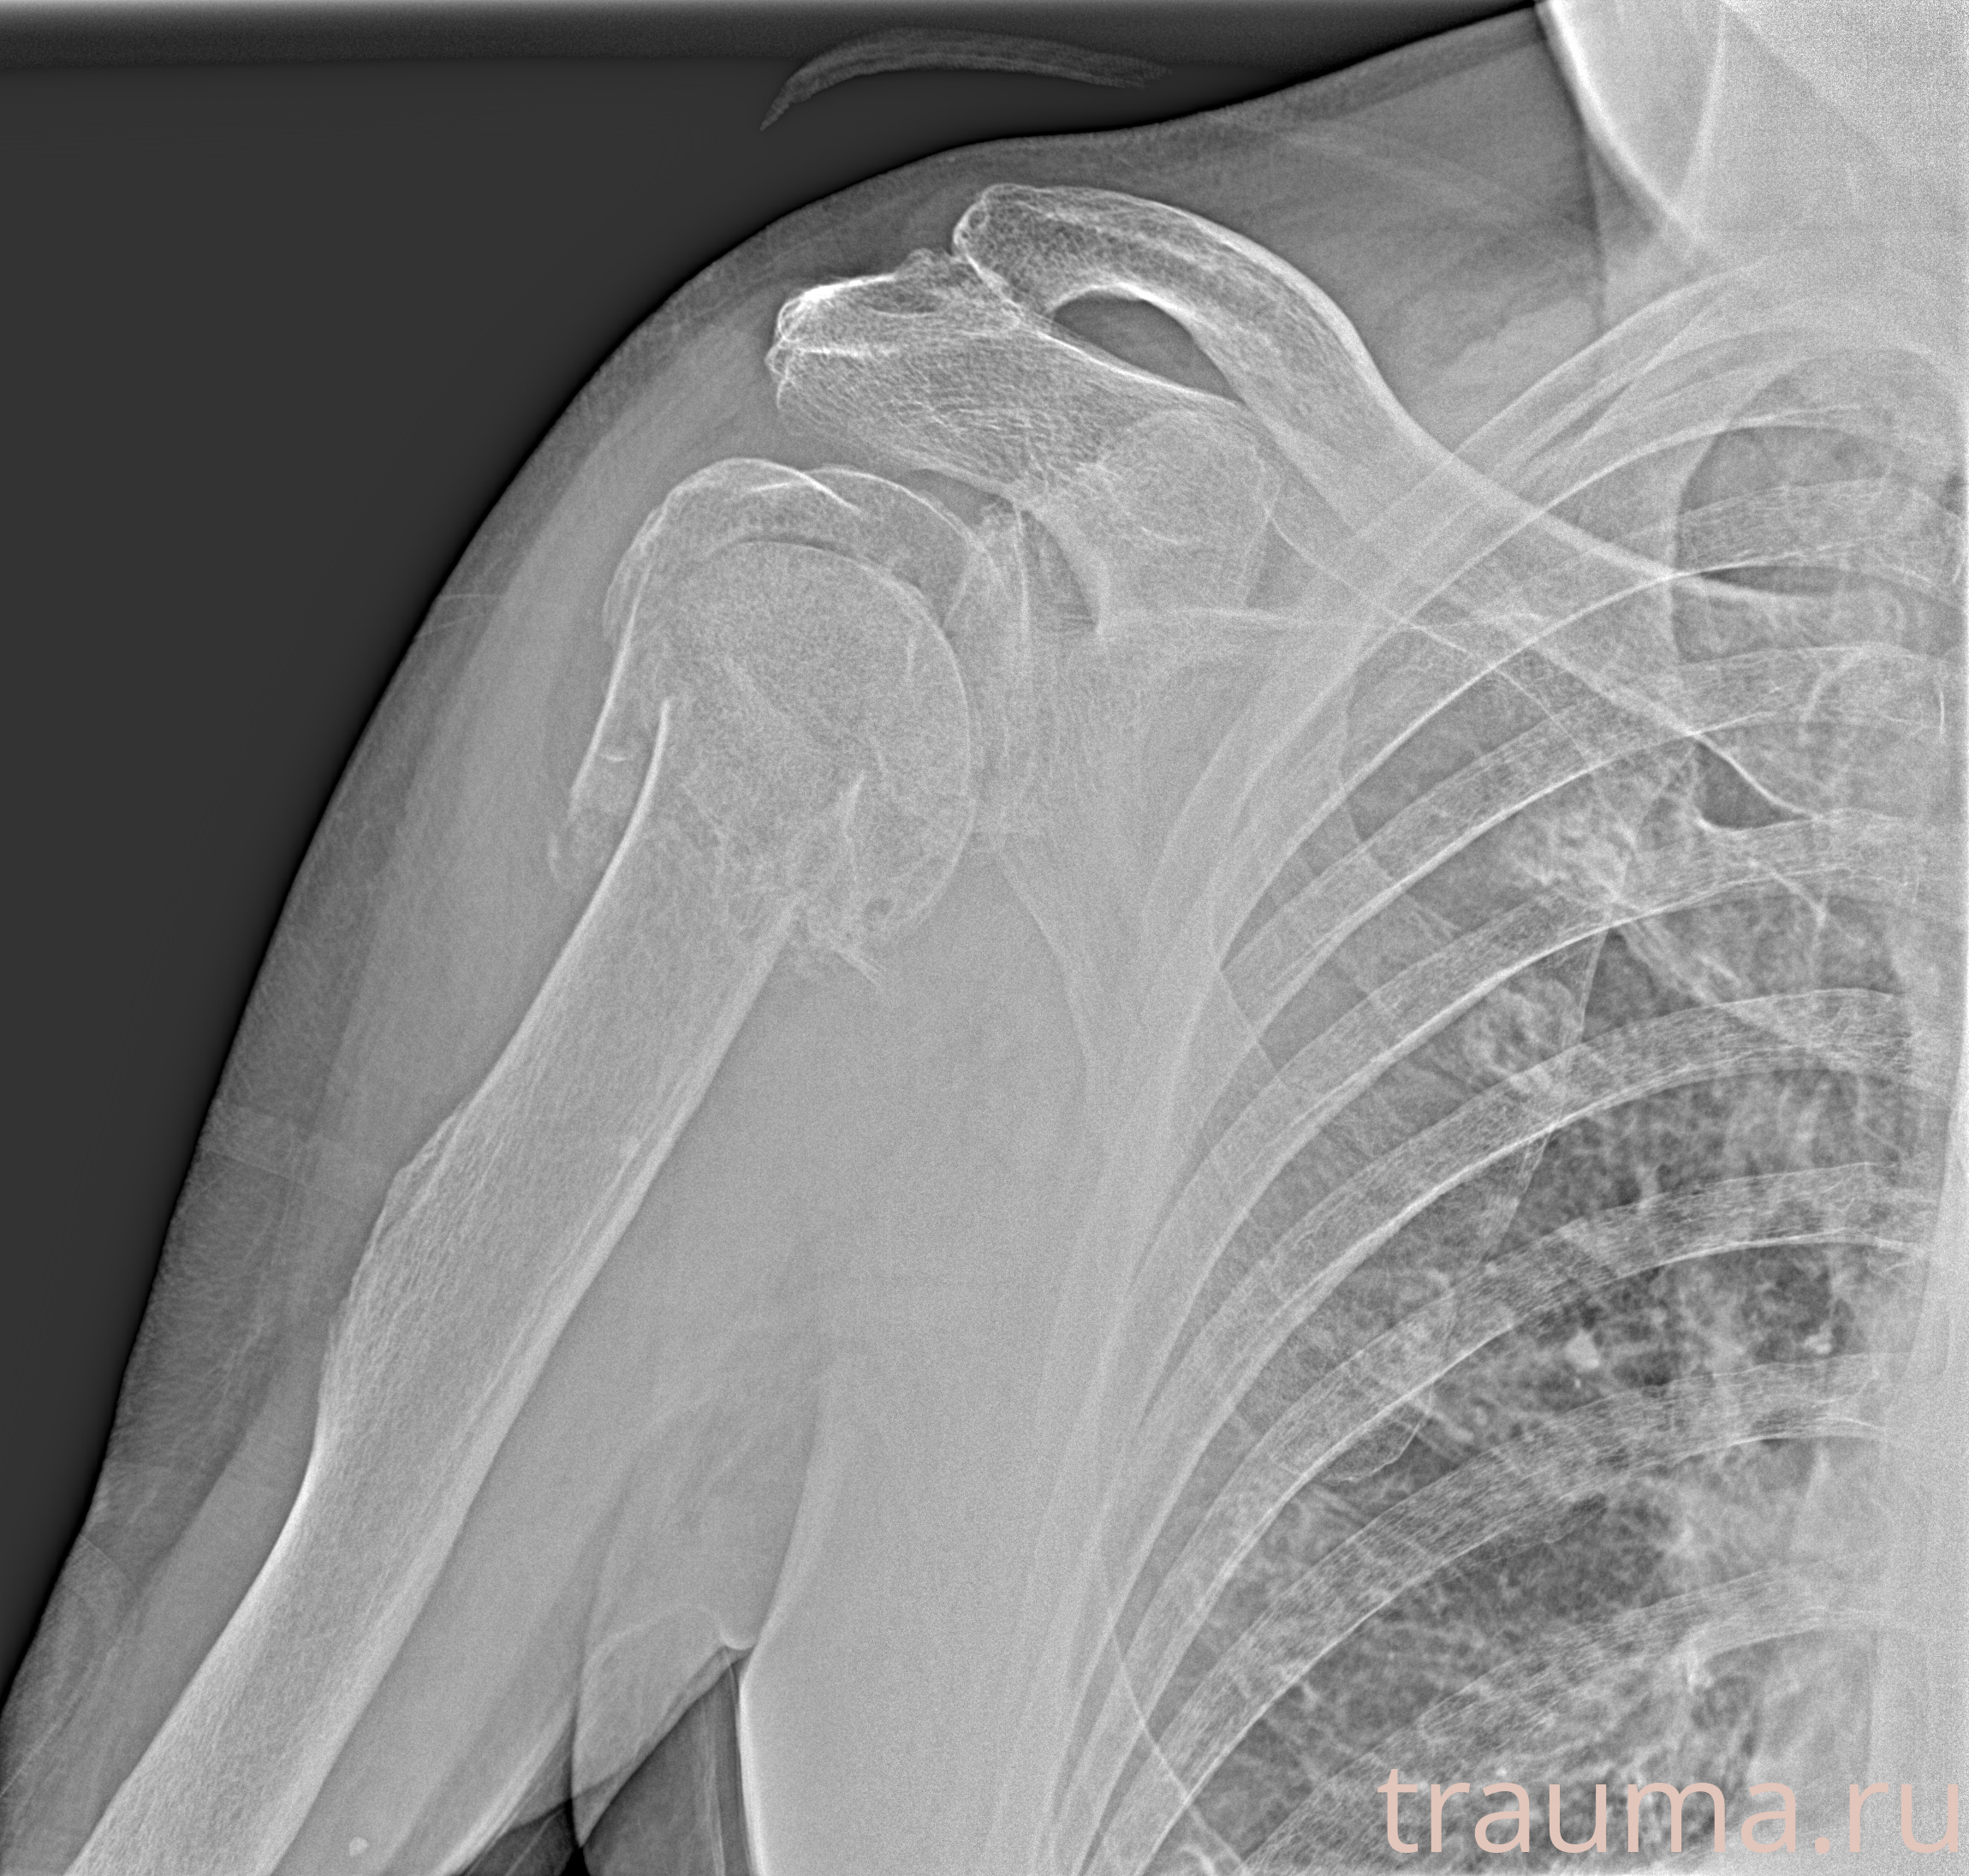

Рентгенограммы

Рентген на дому: по вашему адресу приезжает врач-рентгенолог, травматолог-ортопед с мобильным рентгеновским аппаратом, проводит диагностику травмы или заболевания, делает необходимые рентгенограммы, дает рекомендации по дальнейшему лечению. Получить качественные снимки в домашних условиях возможно благодаря уникальной методике, разработанной МосРентген Центром для института  Склифосовского